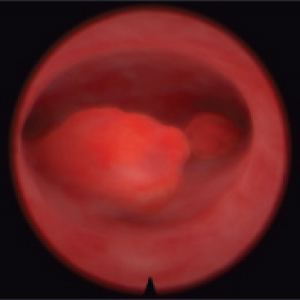

Resectoscope for hysteroscopy

Real resectoscope handle. Pedals for coagulation and electric dissection.